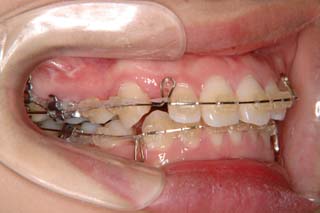

一般的なマルチブラケット装置を用いた治療では、先ずは形状記憶合金のワイヤーで大まかに配列を行い、バネをきかせたワイヤー、堅いワイヤーを使って仕上げていく方法です。

最終仕上げの段階です。かなり太めのワイヤーが入っていますが、このワイヤーの後にオーバーコレクション(元々の歯の捻れが有った場合、後戻りで出てきやすいので、わざと過剰に捻れを治しておく事)を行うための、細めのワイヤーを使う事もあります。